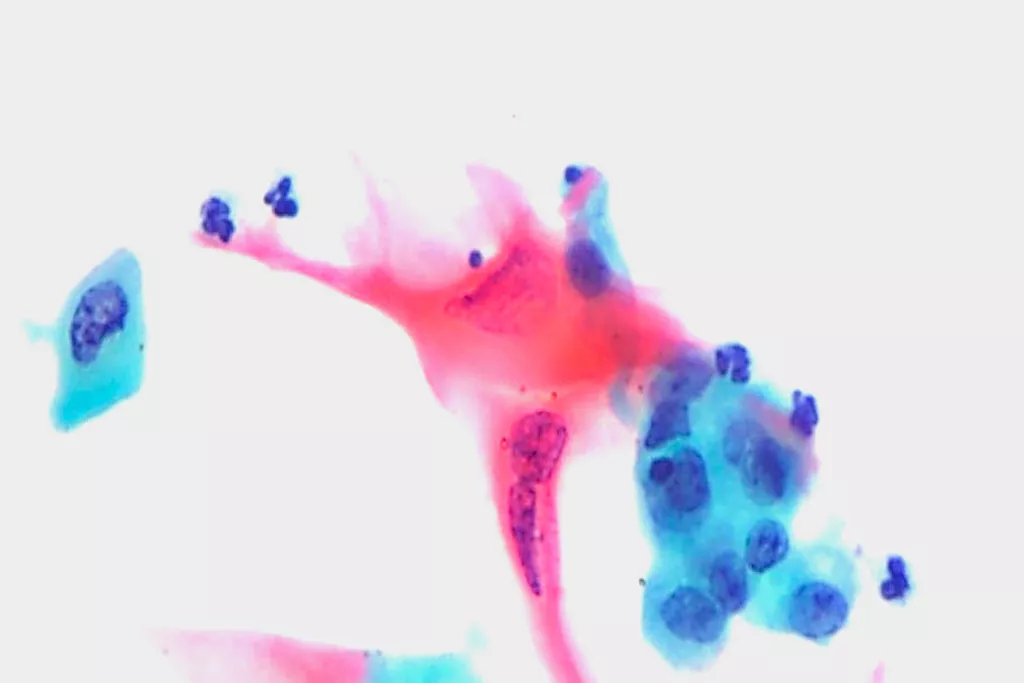

Galleria di immagini9

9. Immagini per gentile concessione del reparto di citopatologia del Llandough Hospital, Galles

Significativamente più efficace rispetto al pap test con striscio per l'individuazione di lesioni intraepiteliali squamose di basso grado (LSIL) e delle lesioni più gravi (HSIL).2

Migliore capacità di individuare le malattie ghiandolari rispetto al pap test convenzionale.2